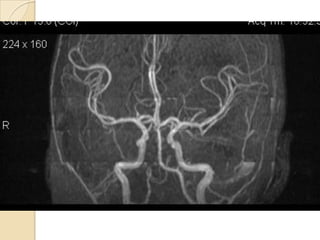

NORMAL MRA

Arteries of the brain (cranial view) - MRA

1. Anterior cerebral artery

2. Anterior communicating artery

3. Basilar artery

4. branches (in insula) of middle

cerebral artery

5. Cavernous portion of internal

carotid artery

6. Cervical portion of internal carotid

artery

7. Genu of middle cerebral artery

8. Intracranial (supraclinoid) internal

9. Middle cerebral artery

10. Ophthalmic artery

11. Petrous portion of internal carotid

12. Posterior cerebral artery

13. Posterior cerebral artery in ambient

cistern

14. posterior cerebral artery in

interpeduncular cistern

15. Posterior communicating artery

16. Posterior inf cerebellar artery.

17. Quadrigeminal portion of posterior

18. Superior cerebellar artery

19. Vertebral artery